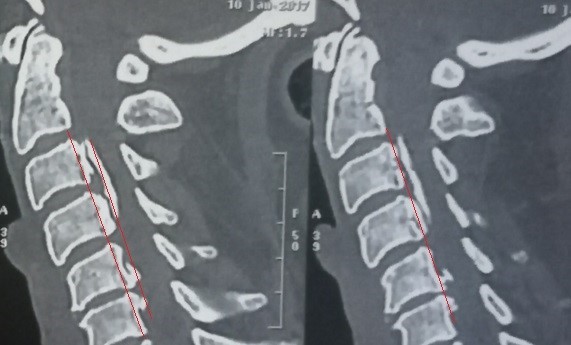

A case of a female patient in the fifth decade of life suffering from quadrilateral weakness and increased neurological reflexes due to her ossification or calcification of the dura mater against the third and fourth cervical vertebrae, and multiple cervical herniated discs as shown on CT and MRI scans.

A successful surgery was performed to expand the cervical nerve canal and stabilize the cervical vertebrae from the back, which resulted in decompression of the spinal cord in the cervical vertebrae, as shown by CT scans and MRI after surgery, and the patient recovered.